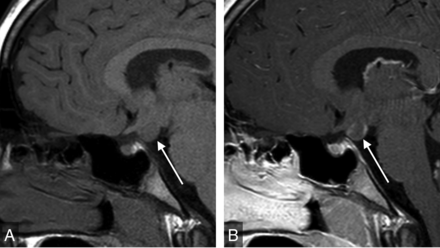

The 3 most common radiologic findings on the studies with abnormal findings were pars intermedia or Rathke cleft cyst (28%, n = 38), a subjectively small anterior pituitary gland (27%, n = 36), and an ectopic or absent posterior pituitary gland (15%, n = 20) (Table 2). A small anterior pituitary gland was determined via subjective assessment of the size/height of the anterior pituitary gland, taking known demographic characteristics (patient age and sex) into account. Microadenoma was identified or suspected in 9 cases (7%). Therapeutic decisions were unaffected by the presence of a suspected microadenoma in all cases. The 7 cases of hypothalamic region pathology included 2 cases of hypothalamic hamartoma, 2 cases of suprasellar arachnoid cyst, 1 case of hypothalamic glioma (Fig 1), 1 case of lipoma of the tuber cinereum, and 1 case of mass effect on the hypothalamus due to extra-axial fluid collections.

Sagittal T1WI of the sella (A) demonstrates a gray matter–isointense suprasellar mass lesion (arrow). Sagittal postgadolinium T1WI (B) shows enhancement, indicating a diagnosis of neoplasm (hypothalamic glioma) rather than hamartoma.